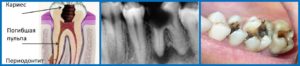

Одной из наиболее частых причин развития заболевания является запущенный пульпит и кариес. Когда обильно скапливается жидкость, наблюдается отечность и характерно выражена гиперемия слизистых оболочек полости рта – такой вид периодонтита называют серозный.

Серозный периодонтит

При обильном скоплении жидкости наблюдается особый вид периодонтита. Он характерен гиперемией слизистых оболочек ротовой полости. Может наблюдаться отечность. Причина развития заболевания — невылеченный пульпит.

Характер боли при остром серозном периодонтите постоянный, ноющий. Цвет зуба меняется, любое прикасание становится нестерпимым. Пациент может четко сказать, какой зуб больной. Есть в наличии кариес, исследование полости не вызывает дискомфорта. Прощупывание десны болезненно.

Увеличения лимфоузлов нет. Рентген не регистрируют патологии верхушки корня.